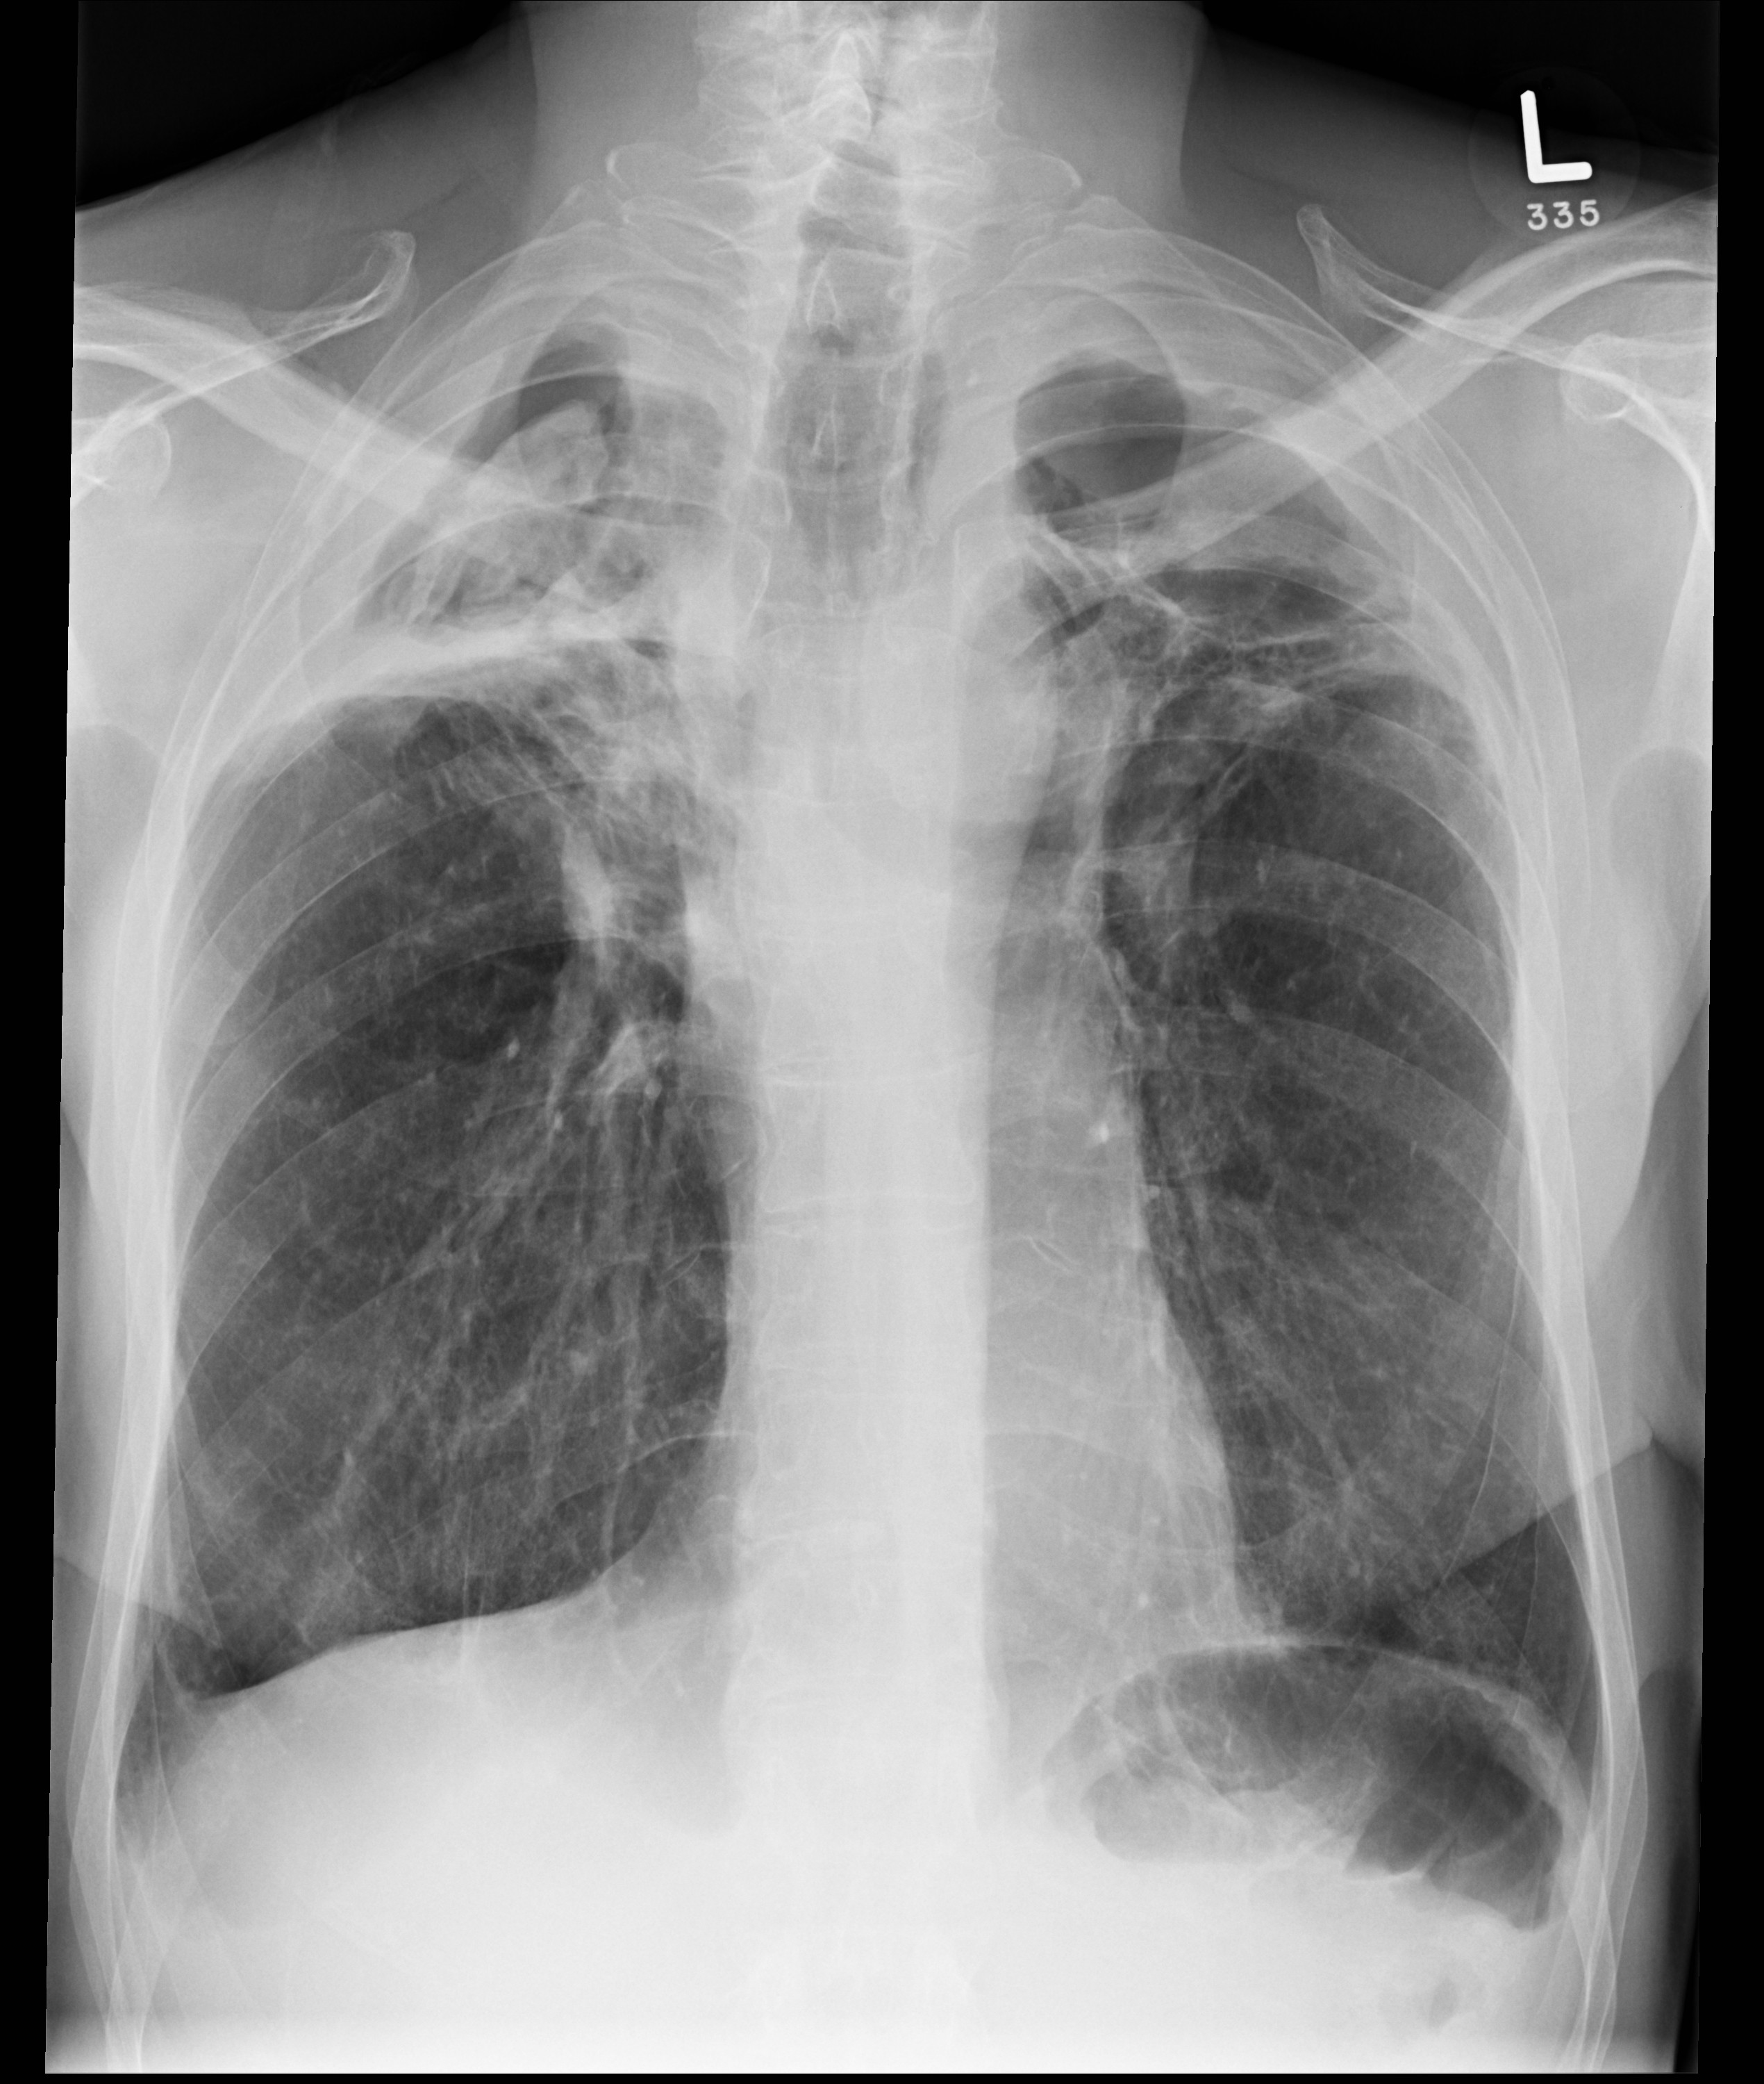

AspergillomaPA